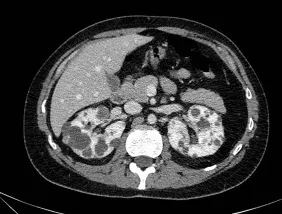

iSGLT2 na Doença Policística Renal: Promessa real ou ilusão terapêutica?